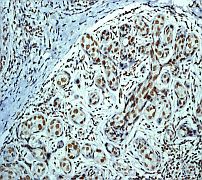

A. Western blot analysis on HeLa cell lysate using anti-Histone Deacetylase 3 RabMAb (Cat. APR07753G), dilution 1:2000.

B. Immunohistochemical analysis of paraffin-embedded human breast carcinoma using anti-Histone deacetylase 3 RabMAb. |